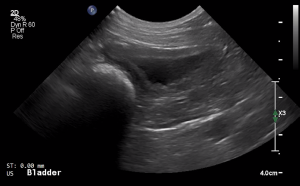

SIMON Ultrasound Database

This ultrasound database is a free resource for students and doctors!

Our collection includes videos of dogs, cats, horses, cows, humans, and many other species!